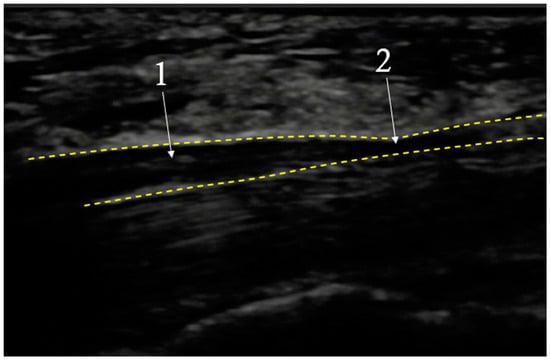

4.2. Lacertus Fibrosus